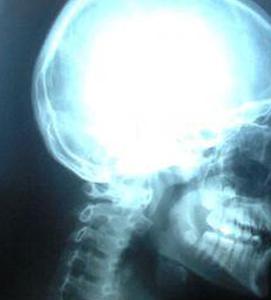

Когда вы идете в кабинет врача на рентген, ваше тело бомбардируется этими волнами, и они действительно вызывают временные повреждения. Однако это минимально, и ваше тело может легко восстановиться после этого повреждения без особых проблем, если вы не будете часто делать рентген. Напротив, вы ежедневно подвергаетесь воздействию излучения сотового телефона, и оно находится в непосредственной близости от очень важной части вашего тела: мозга. Хотя кратковременное воздействие, кажется, имеет минимальный эффект, есть доказательства, подтверждающие утверждение о том, что длительное воздействие связано с раком. Это не обязательно означает, что опухоли вызваны сотовыми телефонами, это может быть взаимосвязь.